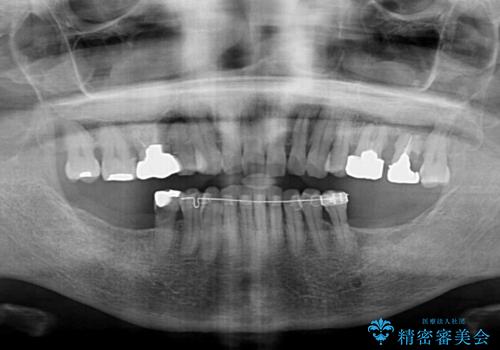

- インプラント治療を前提に下顎の部分矯正を始めたものの、そのまま長い間放置しているとのことで来院された患者様です。

全体的に歯肉が腫れており、歯周病により抜歯をしなければならない歯がある状態でした。

矯正治療を仕上げ、必要に応じて歯周外科処置を行い、適宜インプラントを埋入しながら咬み合わせを回復させていくこととしました。

最終的に奥歯はオールセラミッククラウンによる補綴治療を行うこととしました。